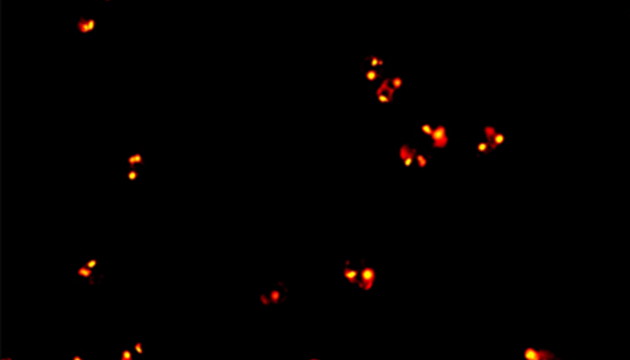

CTC檢測(cè)用于上皮腫瘤,如胃腸癌、皮膚癌等。檢測(cè)分四步:富集、CD45染白細(xì)胞、CK染CTC、DAPI染核。有DAPI、CK熒光且無(wú)CD45熒光,大核細(xì)胞為CTC;有DAPI、CD45熒光為白細(xì)胞。

CTC檢測(cè)面臨儀器通用性差、多色熒光閱片繁瑣及高靈敏度成像難三大難點(diǎn)。新技術(shù)如微流控芯片有望取代專用儀器,提升富集效率。使用電動(dòng)熒光顯微鏡搭配微流控,可更高效率進(jìn)行CTC成像和閱片。另外為滿足高靈敏度成像需求,建議配置優(yōu)質(zhì)LED光源、高效濾光片、半復(fù)消色差或以上物鏡及高靈敏度相機(jī)。